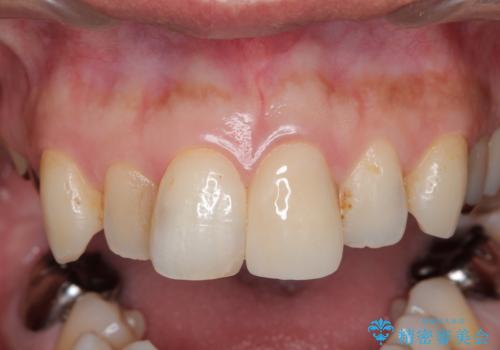

転んで折れた前歯セラミック治療で審美改善

- 15.4万円(ジルコニアクラウン・仮歯・ファイバーコア)費用は治療当時の料金となります

周囲の歯と調和した審美的な仕上がりに満足いただくことができました。